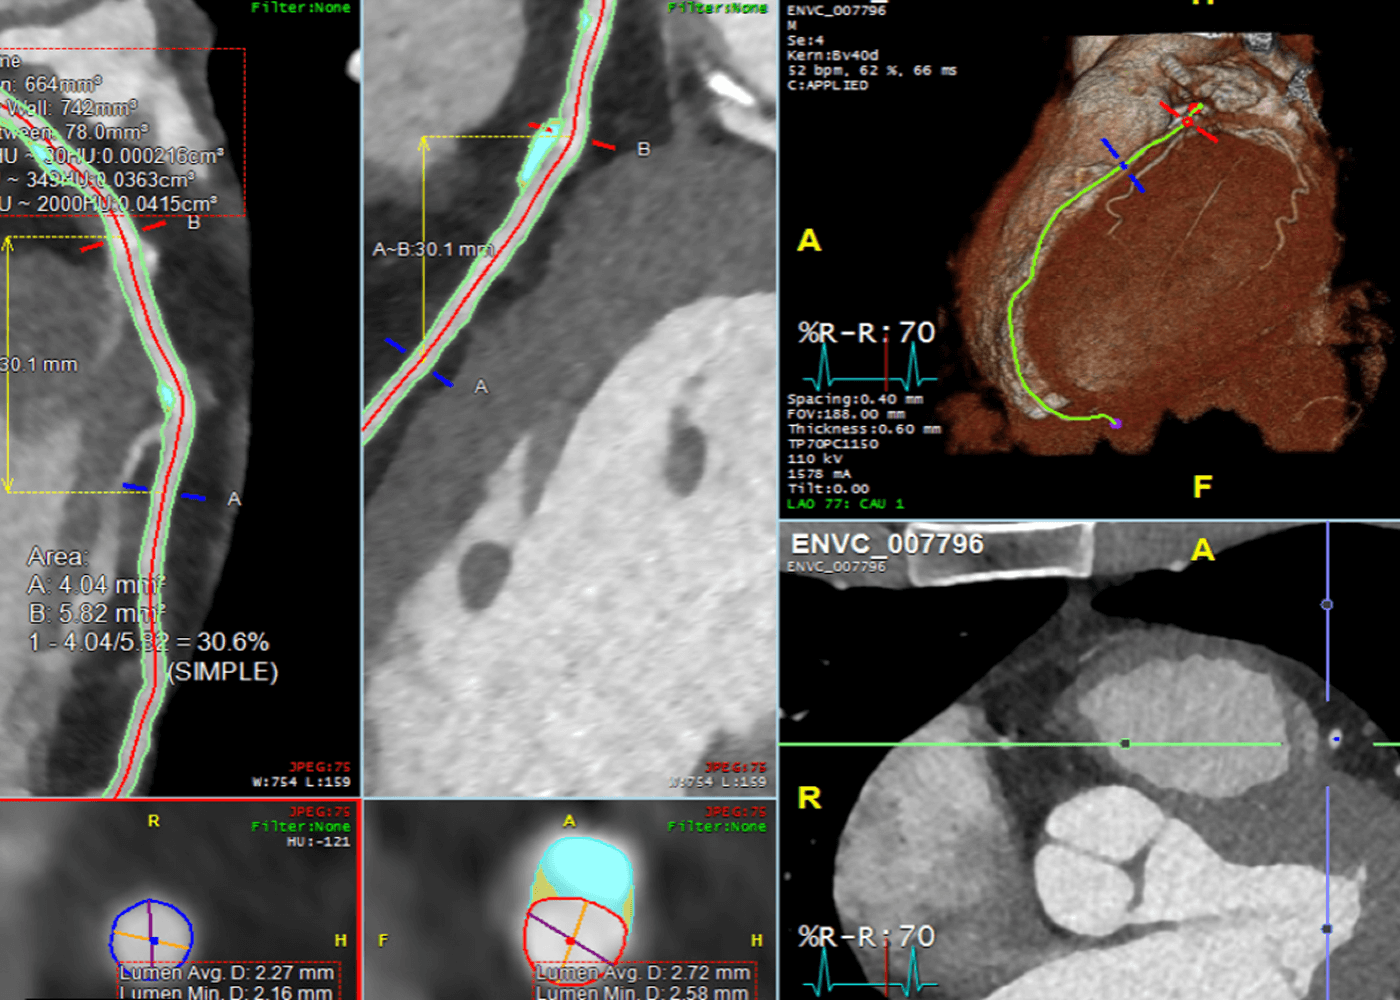

Coronary arteries segmentation with wall plaques analysis